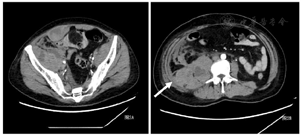

实验室检查:血气分析(FiO2:40%):pH7.416, PaO2:117.3mmHg(氧合指数:293),血常规:白细胞:4.50×109/L;中性粒细胞占:91.8%;淋巴细胞占:5.4%。血红蛋白:144g/L;血小板:273×109/L;心肌酶:肌酸激酶219.4 U/L,肌钙蛋白I 0.09ug/L,肌红蛋白41.0ug/L;乳酸脱氢酶490.5U/L;血沉:65mm/h;血清铁蛋白:1788ng/mL。抗核抗体:1:100,胞浆颗粒型,肌炎谱:抗MDA5-IgG(++)、抗Ro52-IgG (+++);胸部高分辨CT(HRCT)示:双下肺分布实变影,伴有肺容积缩小(图1)。

甲泼尼龙500mg×3天,逐渐减量(250mg×3天、160mg×3天、80mg×5天);环磷酰胺0.8gqw×2次;余予以全覆盖抗感染以及吡非尼酮600mg tid /d抗纤维化治疗。患者经过治疗后气促症状好转。患者于9月20日出现右侧大腿及臀部疼痛,未见红肿,皮温不高,无压痛。9月21日出现腹痛,压痛及反跳痛明显。急查血常规:红细胞:2.8*1012/L,血红蛋白:86g/L;凝血功能:PT:14.2秒、APTT:50.1秒、纤维蛋白原1.76g/L。综合上述临床表现,不排除腹腔出血可能性,行床旁B超提示腹膜后混合回声区,不排除脓肿或血肿。为进一步明确诊断,于当日申请急诊腹部CT,提示右侧腹膜后及右侧腹直肌多发血肿,周围脂肪间隙及腹膜增厚(图2)。请介入科会诊后建议介入治疗,因患者一般情况差,家属拒绝进一步治疗自动出院后随访患者死亡。